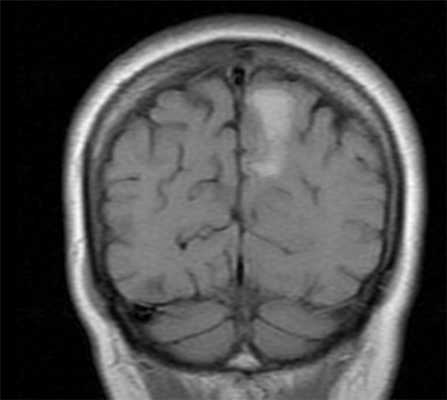

МРТ головного мозга. Корональная Т1-взвешенная МРТ с контрастированием. Кистозная гемангиобоастома.

Гемангиобластома представляет собой доброкачественную сосудистую опухоль. В целом ее частота составляет 1-2% от внутричерепных новообразований и 7-12% от опухолей задней черепной ямки у взрослых. Встречается чаще у мужчин в возрасте 30-50 лет. Мозжечек - типичная локализация гемангиобластомы, причем обычно она расположена по его периферии. Множественные гемангиобластомы при спорадических случаях наблюдаются в 5%, при болезни Гиппель -Линдау в 30-60%. Клинические проявления отмечаются при больших размерах опухоли и состоят из головных болей, рвоты, атаксии и полицитэмии в связи с тем, что опухоль вырабатывает эритропоэтин. При МРТ головного мозга на Т1-зависимых МРТ узел немного гипоинтенсивен, на Т2-зависимых МРТ гиперинтенсивен. Участки отсутствия сигнала соответствуют расширенным сосудам в опухоли и вокруг нее. Еще лучше сосуды видны при МР ангиографии. Опухолевый узел окружен кистой. Редко встречаются гемангиобластомы не окруженные кистой, а также содержащие кисту внутри узла. При МРТ сигнал от кисты зависит от содержимого, которое может быть с примесью белка и крови. Солидный компонент (узел) при МРТ с введением контраста хорошо контрастируется.